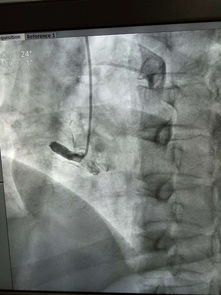

3. 诊断的“金标准”:组织病理学检查:当影像学发现高度可疑的结节时,为了最终确诊,需要进行病理活检。常用方法包括:

支气管镜检查:适用于靠近大气道的病灶,可直接观察并钳取组织^。

CT引导下经皮肺穿刺活检:适用于外周型肺结节,在CT实时引导下用细针穿刺获取组织^。

胸腔镜手术活检:既能明确诊断,对于早期肺癌也可同时完成治疗性切除^。